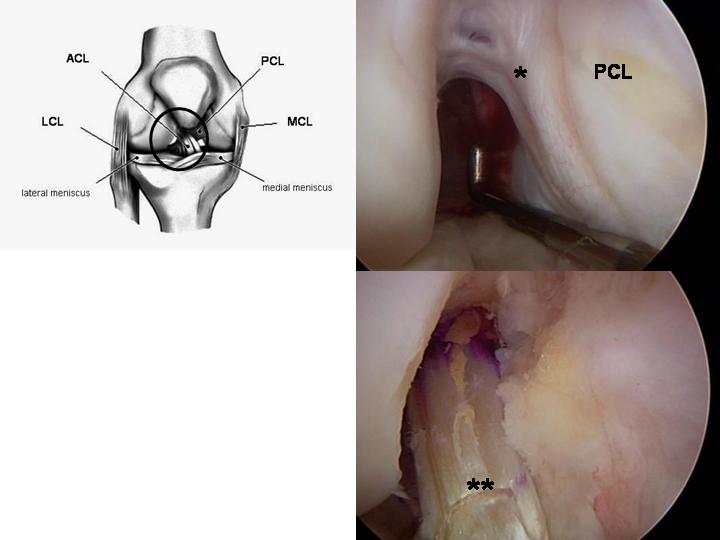

La seconda parte di ricostruzione del crociato si effettua interamente in artroscopia. Una volta “pulito” il ginocchio dai residui del vecchio legamento, vengono creati un tunnel nella tibia e uno nel femore, all’interno dei quali viene fatto passare il nuovo legamento crociato. Una volta verificata la sua corretta posizione e funzionalità, il nuovo crociato viene in genere fissato a livello del femore con una placchetta, ed a livello della tibia con una vite.

sopra crociato rotto e sotto quello ricostruito